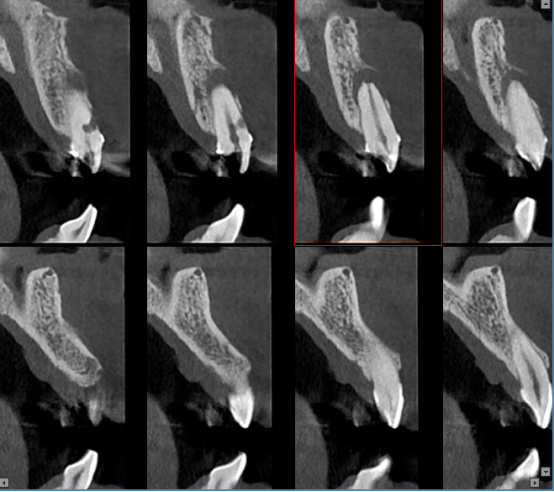

根管和牙周治疗过程中,提供牙根位置、角度、是否牙裂病变及下颌管、牙周围组织高清图像,以便于分辨治疗每个细节,做出精确诊断以及有效治疗方案。